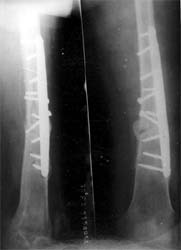

股骨远端骨折术后10年,4次手术均失败。经带锁髓内钉内 固定、植骨,骨生长因子和骨髓细胞注射,成功治愈